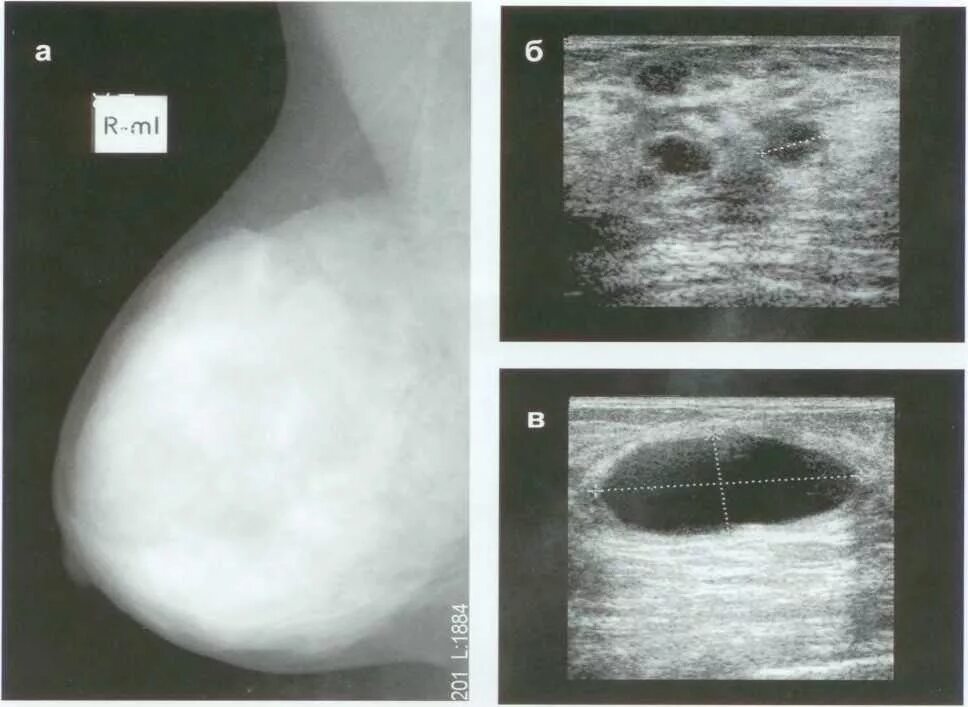

Диффузно фиброзно кистозные изменения